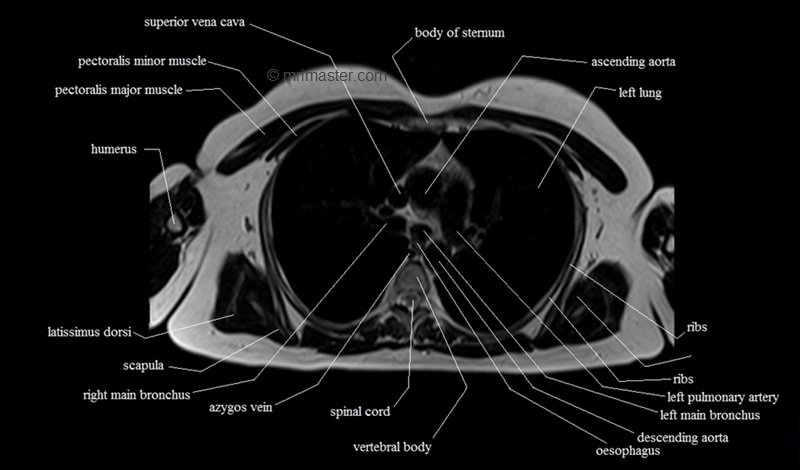

MRI Axial Cross Sectional Anatomy of Chest

This MRI chest (thorax) axial cross sectional anatomy tool is absolutely free to use. Use the mouse scroll wheel to move the images up and down, or alternatively, use the tiny arrows (→) on both sides of the image to navigate through the images. For a more detailed view, double-click the image to view it in full screen, and use the menu in the top right-hand corner to view individual slides or play them in a loop.